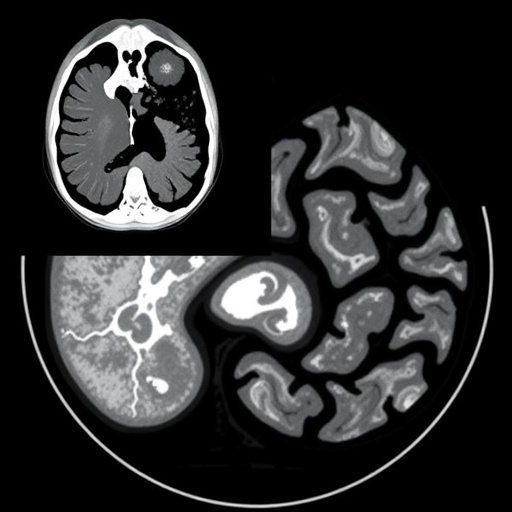

Pedunculopontine nucleus (PPN), situated in the brainstem, is a fundamental hub for cholinergic neurons known to regulate arousal, motor control, and REM sleep. The cholinergic projections emanating from this nucleus reach the thalamus, a central relay station in the brain that modulates cortical activity and sensory information processing. In this study, the authors employed advanced neuroimaging and electrophysiological techniques alongside post-mortem histological analysis to map and characterize the integrity of the pedunculopontine-thalamic cholinergic pathway in subjects diagnosed with RBD.

The methodology uncovered significant degeneration and altered connectivity in cholinergic projections implicating a breakdown in the neural circuits responsible for REM sleep muscle atonia. Using targeted tracers and immunohistochemical markers, the study detailed how cholinergic terminal loss correlated with the severity of REM sleep muscle tone abnormalities. Functional MRI scans of RBD patients revealed decreased connectivity between the PPN and thalamic nuclei, suggesting a functional impairment that mirrors the structural degeneration observed microscopically.

Additionally, the integration of multi-modal imaging and neuropathological data sets a new standard for investigating brainstem-cholinergic circuits in human disease. This comprehensive approach enables precise localization of affected pathways and correlates these findings with clinical symptomatology, supporting a biomarker-driven model for early diagnosis and individualized treatment strategies in RBD and Parkinson’s disease.